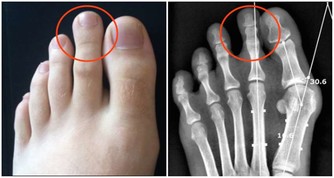

4. 肥胖者

肥胖會引起發炎,而發炎在癌症發展的各個階段如癌變、侵襲、轉移中都扮演重要的角色。

自己胖不胖,腰圍就能給出答案。男性腰圍建議不超過90公分,女性腰圍建議不超過80公分。